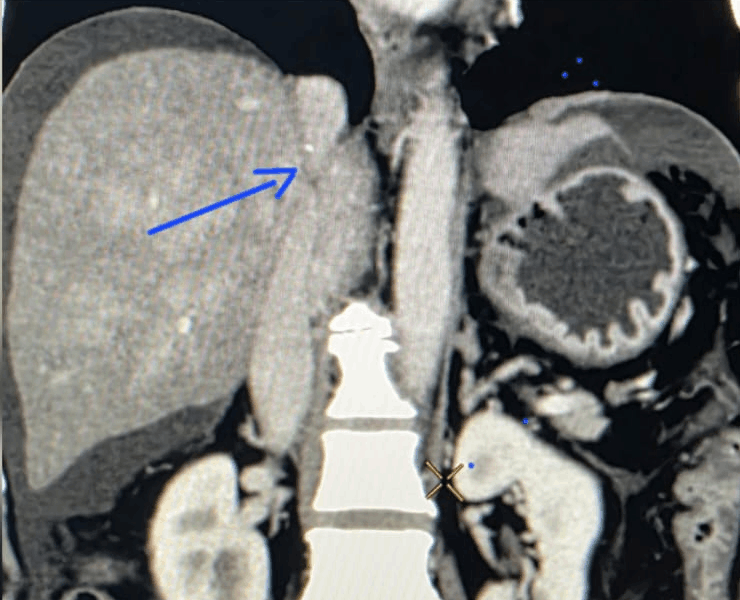

Advanced liver disease and portal hypertension can lead to severe complications such as refractory ascites (fluid in the abdomen), pleural effusion around the lungs and Budd–Chiari syndrome with blocked hepatic veins and inferior vena cava (IVC).

- Budd–Chiari syndrome with blocked hepatic veins/IVC

Before and after procedure, we did DIPS procedure on this patient